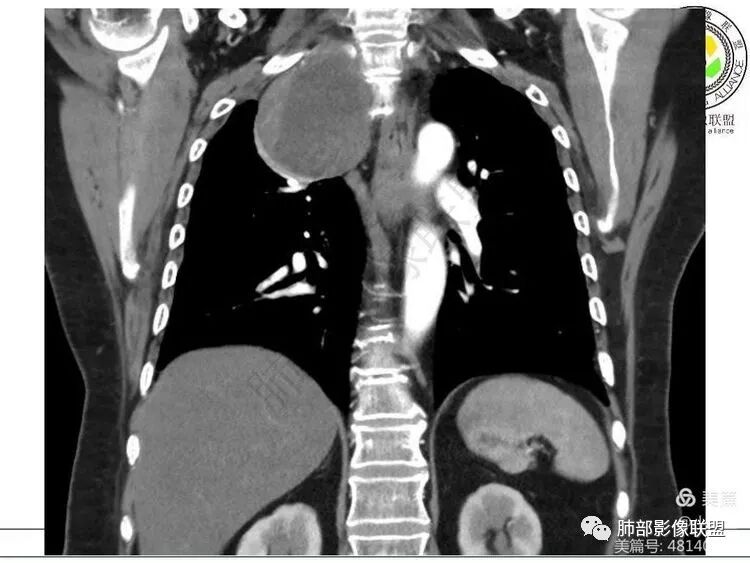

血管、压缩肺组织病灶的长轴:上下走形

推压血管,进入颈部

南边:支持:神经源性,从病灶的形态突入颈部,跨多区域

1. 右上胸廓入口区类椭圆形块影,边界清楚光整,纵向“嵌顿”于颈根部及上纵隔,向上推移右锁骨下动静脉,向外下方推移上肺胸膜及肺组织(肺血管、支气管),向前推移上腔静脉,界限清楚。

神经鞘瘤是周围神经最常见的肿瘤,起源于神经鞘膜的施万细胞,生长缓慢,包膜完整,与起源神经紧密相连,绝大多数为良性,恶性罕见;纵隔内神经源性肿瘤90%发生于后纵隔,发生在交感神经链或肋间神经的椎旁;偶尔,神经鞘瘤可位于中纵隔或前纵隔,最常见的发生于迷走神经,其次是喉返神经、膈神经等。所以神经源性肿瘤很重要一点在于解剖,一般只要存在神经组织,都可以发生神经源性肿瘤;后纵隔神经鞘瘤最常见的位置是脊神经刚出椎间孔的位置,并沿着肋间神经分布,所以一般横径大,上下径小,而且来源于神经根的可呈哑铃状跨越椎管内外生长;而来源于前或中纵隔神经的迷走神经或喉返神经等是上下走形,所以神经鞘瘤常表现为上下径长;神经鞘瘤在病理上包括A区和B区,Antoni A区富含细胞,密度较高,Antoni B区含有较多粘液成分,密度较低,可见囊变、出血,如果出血,血肿可见机化、钙化。

中纵隔迷走神经走形

中纵隔右侧迷走神经来源神经鞘瘤

中纵隔神经鞘瘤(迷走神经走形,上下径大于左右径)